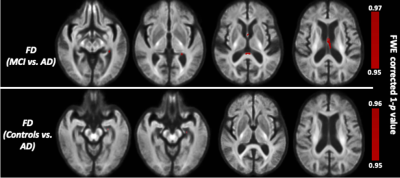

The whole-brain FBA showed significant reduction in FD in individuals with AD compared to MCI, in regions including splenium of corpus collosum, fornix, and the left uncinate fasciculus. Furthermore, AD showed significant reduction in FD in the left uncinate fasciculus compared to controls. Figure 2 shows WM tracts where significant (FWE corrected p <0.05) reductions in FD were observed.We observed subtle reduction in FD and FDC metrics (although the differences were not statistically significant after FWE corrections) in regions including corpus callosum (bilaterally), forceps majors (bilaterally), and uncinate fasciculus in AD compared to MCI. The reduction in FD was more pronounced compared to the reduction in FDC (Figure 3).Furthermore, FD and FDC were observed to be reduced (although not statistically significant after FWE correction) in regions including uncinate and the arcuate fasciculus (bilaterally) in AD relative to controls (Figure 4). We did not observe notable difference in FC in any groups. There were no reductions in FBA measures in MCI relative to controls.

Figure 2: Fibre tract-specific reductions in Alzheimer’s disease from whole-brain FBA. White matter regions showing significant reductions (p<0.05) in FD are superimposed onto the population template.